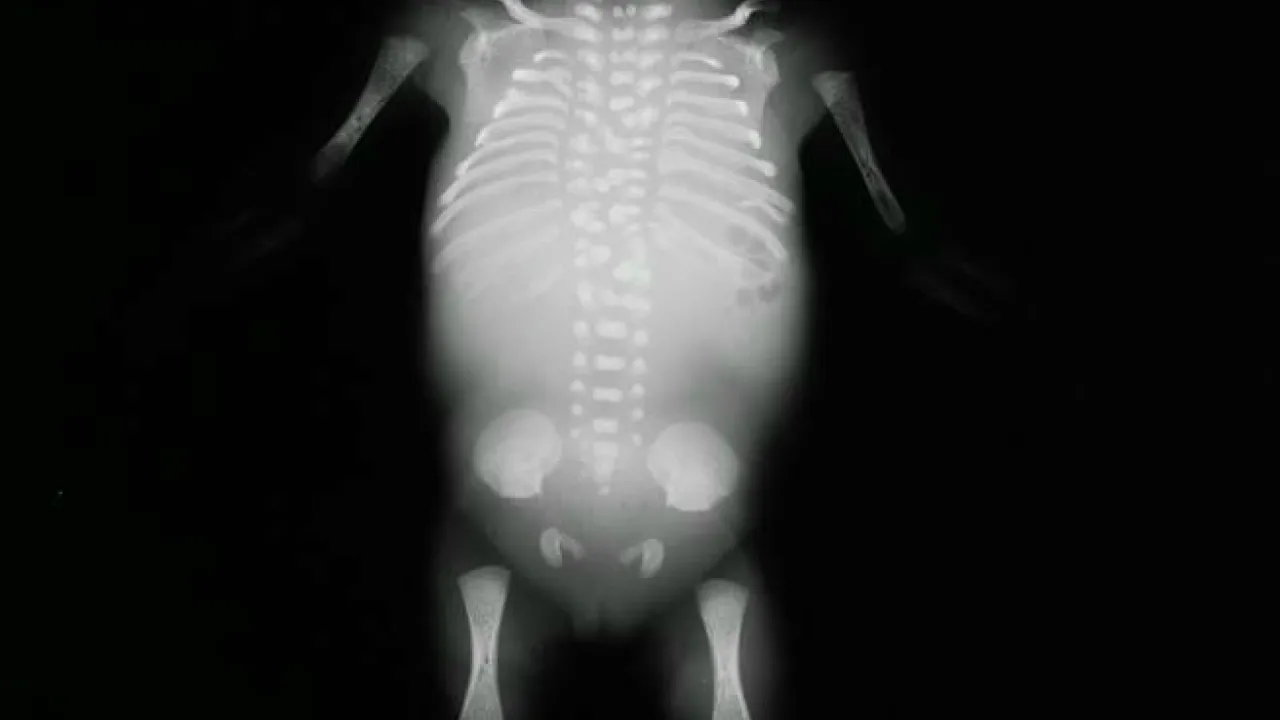

Bones, Hypophosphatasia

Bones, Hypophosphatasia, Sibling